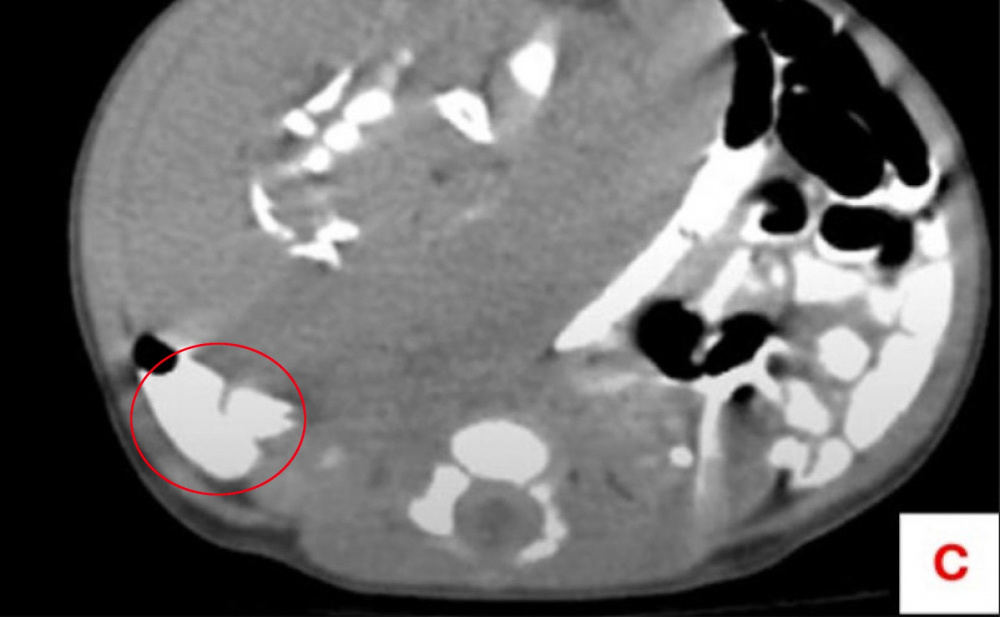

4D УЗИ показало, что в брюшной полости ребенка есть некая масса размером 8 на 6 см.

КТ с контрастированием установило, что это мягкие ткани и деформированные части скелета, похожие на длинные кости, ребра, позвонки, кости таза. Близнец-паразит получал питательные вещества от крупной артерии в теле ребенка.Его извлекли из младенца во время лапаратомии (операции, при которой совершается надрез в области брюшной полости). Капсула с телом близнеца-паразита располагалась возле печени юной пациентки. В капсуле находились жир, деформированные ткани, две конечности и пуповина. Исследование под микроскопом выявило наличие зрелой эмбриональной ткани, кожи и кишечника.